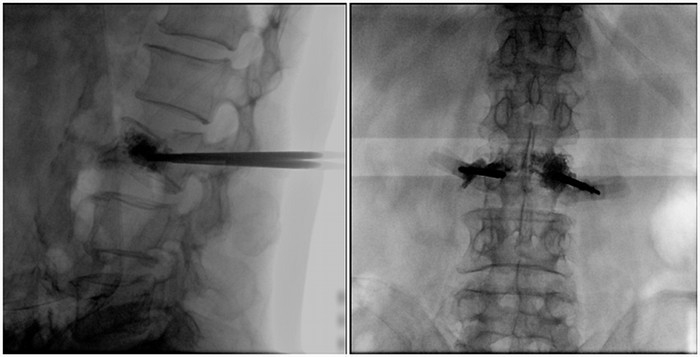

普愛醫(yī)療大平板一體式移動(dòng)C臂采用30cm×30cm的平板探測器,能在手術(shù)過程中,為醫(yī)生提供更廣闊的視野范圍,帶給醫(yī)生更全面的影像信息。在進(jìn)行脊柱類手術(shù)時(shí),一次曝光即可呈現(xiàn)全節(jié)段腰椎,避免因?yàn)槌氏癫蝗鴮?dǎo)致重復(fù)曝光,不僅提高了手術(shù)效率,而且避免醫(yī)生吸收過量的輻射。

大平板一體式移動(dòng)C臂采用一體化設(shè)計(jì),將工作站與C臂合二為一,摒棄了二者之間的線纜連接,真正做到工作站與C臂的無縫銜接,其靈動(dòng)設(shè)計(jì),只需一人即可移動(dòng)設(shè)備,同時(shí)大幅節(jié)省了占地空間,有效解決手術(shù)室空間擁擠以及手術(shù)間轉(zhuǎn)運(yùn)設(shè)備的問題,為醫(yī)生患者提供高質(zhì)量的治療,同時(shí)增加手術(shù)效率。